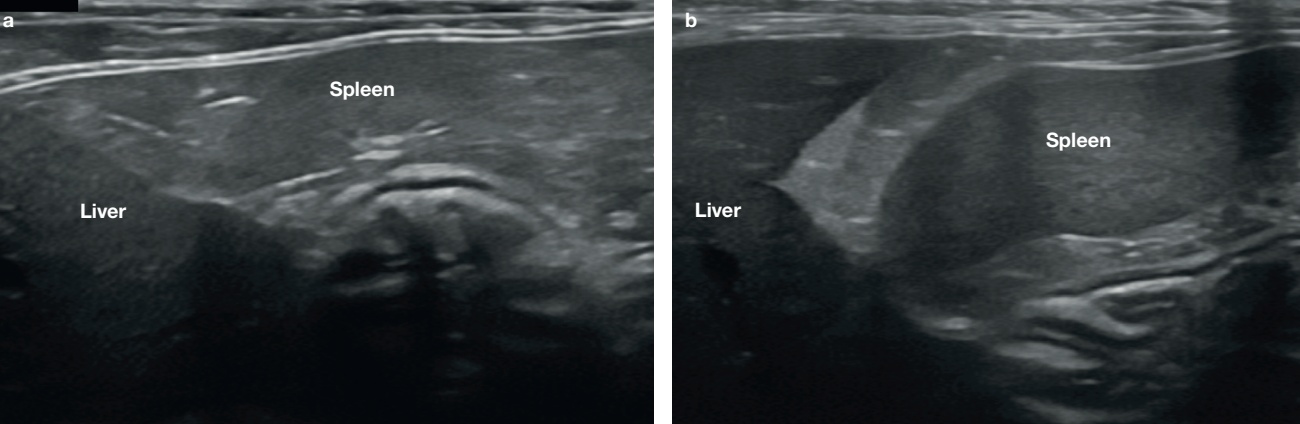

비장의 에코성(echogenicity)은 간과 신장의 에코성과 비교에서 간보다는 높고, 신장보다는 약간 낮습니다(그림 3). 2), 3)